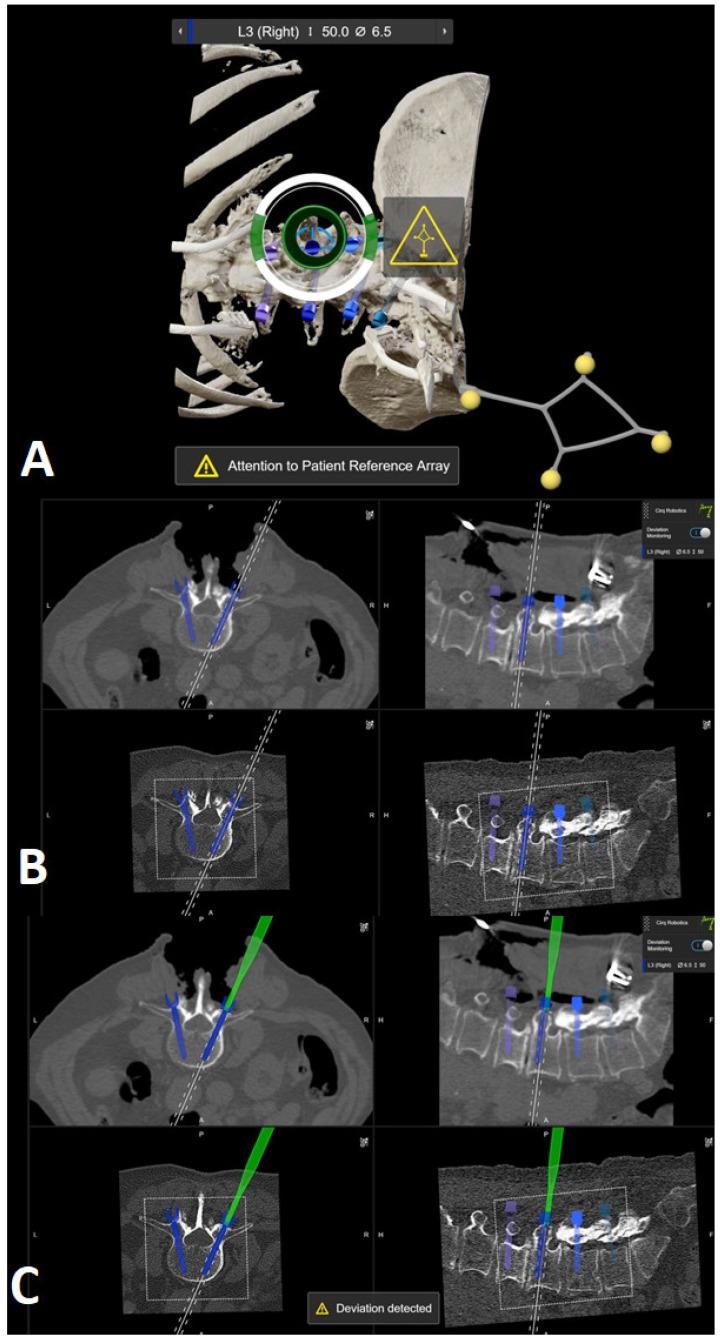

The aim of this study is to present the initiation of robotic-guided (RG) spine surgery into routine clinical care at a single center with the use of intraoperative CT (iCT) automatic registration-based navigation. The workflow included iCT with automatic registration, fusion with preoperative imaging, verification of preplanned screw trajectories, RG introduction of K-wires, and the insertion of pedicle screws (PSs), followed by a control iCT scan. All patients who underwent RG implantation of pedicle screws using the Cirq robotic arm (BrainLab, Munich, Germany) in the thoracolumbar spine at our department were included in the study. The accuracy of the pedicles screws was assessed using the Gertzbein-Robbins scale (GRS). In total, 108 patients (60 female, mean age 68.7 ± 11.4 years) in 109 surgeries underwent RG PS placement. Indications included degenerative spinal disorders ( = 30 patients), spondylodiscitis ( = 24), tumor ( = 33), and fracture ( = 22), with a mean follow-up period of 7.7 ± 9 months. Thirty-seven cases (33.9%) were performed percutaneously, and all others were performed openly. Thirty-three operations were performed on the thoracic spine, forty-four on the lumbar and lumbosacral spine, thirty on the thoracolumbar, one on the cervicothoracic spine, and one on the thoracolumbosacral spine. The screws were inserted using a fluoroscopic (first 12 operations) or navigated technique (latter operations). The mean operation time was 228.8 ± 106 min, and the mean robotic time was 31.5 ± 18.4 min. The mean time per K-wire was 5.35 ± 3.98 min. The operation time was lower in the percutaneous group, while the robot time did not differ between the two groups. Robot time and the time per K-wire improved over time. Out of 688 screws, 592 were GRS A screws (86.1%), 54 B (7.8%), 22 C (3.2%), 12 D (1.7%), and 8 E (1.2%). Seven screws were revised intraoperatively, and after revision, all were GRS A. E screws were either revised or removed. In the case of D screws, screws located at the end of the construct were revised, while so-called in-out-in screws in the middle of the construct were not revised. Brainlab's Cirq Robotic Alignment Module feature enables placement of pedicle screws in the thoracolumbar spine with high accuracy. A learning curve is shown through improvements in robotic time and time per K-wire.

本研究的目的是介绍在单一中心将机器人引导(RG)脊柱手术引入常规临床护理,采用术中CT(iCT)基于自动配准的导航技术。工作流程包括iCT自动配准、与术前影像融合、预规划螺钉轨迹验证、RG引导下克氏针置入以及椎弓根螺钉(PS)植入,随后进行对照iCT扫描。本研究纳入了在我们科室接受使用Cirq机器人手臂(德国慕尼黑BrainLab公司)在胸腰椎进行RG椎弓根螺钉植入的所有患者。使用Gertzbein-Robbins量表(GRS)评估椎弓根螺钉的准确性。总共109例手术中的108例患者(60例女性,平均年龄68.7±11.4岁)接受了RG PS置入。适应证包括退行性脊柱疾病(n = 30例患者)、脊椎间盘炎(n = 24)、肿瘤(n = 33)和骨折(n = 22),平均随访期为7.7±9个月。37例(33.9%)为经皮手术,其余均为开放手术。胸椎手术33例,腰椎和腰骶椎手术44例,胸腰椎手术30例,颈胸椎手术1例,胸腰段手术1例。螺钉采用透视技术(前12例手术)或导航技术(后序手术)置入。平均手术时间为2(28.8±106)分钟,平均机器人操作时间为31.5±18.4分钟。每根克氏针的平均时间为5.35±3.98分钟。经皮组的手术时间较短,而两组的机器人操作时间无差异。机器人操作时间和每根克氏针的时间随时间有所改善。在688枚螺钉中,592枚为GRS A级螺钉(86.1%),54枚为B级(7.8%),22枚为C级(3.2%),12枚为D级(1.7%),8枚为E级(1.2%)。7枚螺钉在术中进行了翻修,翻修后均为GRS A级。E级螺钉要么进行了翻修,要么被取出。对于D级螺钉,位于结构末端的螺钉进行了翻修,而结构中间的所谓进出式螺钉未进行翻修。Brainlab公司的Cirq机器人对准模块功能能够高精度地在胸腰椎置入椎弓根螺钉。通过机器人操作时间和每根克氏针时间的改善显示出学习曲线。